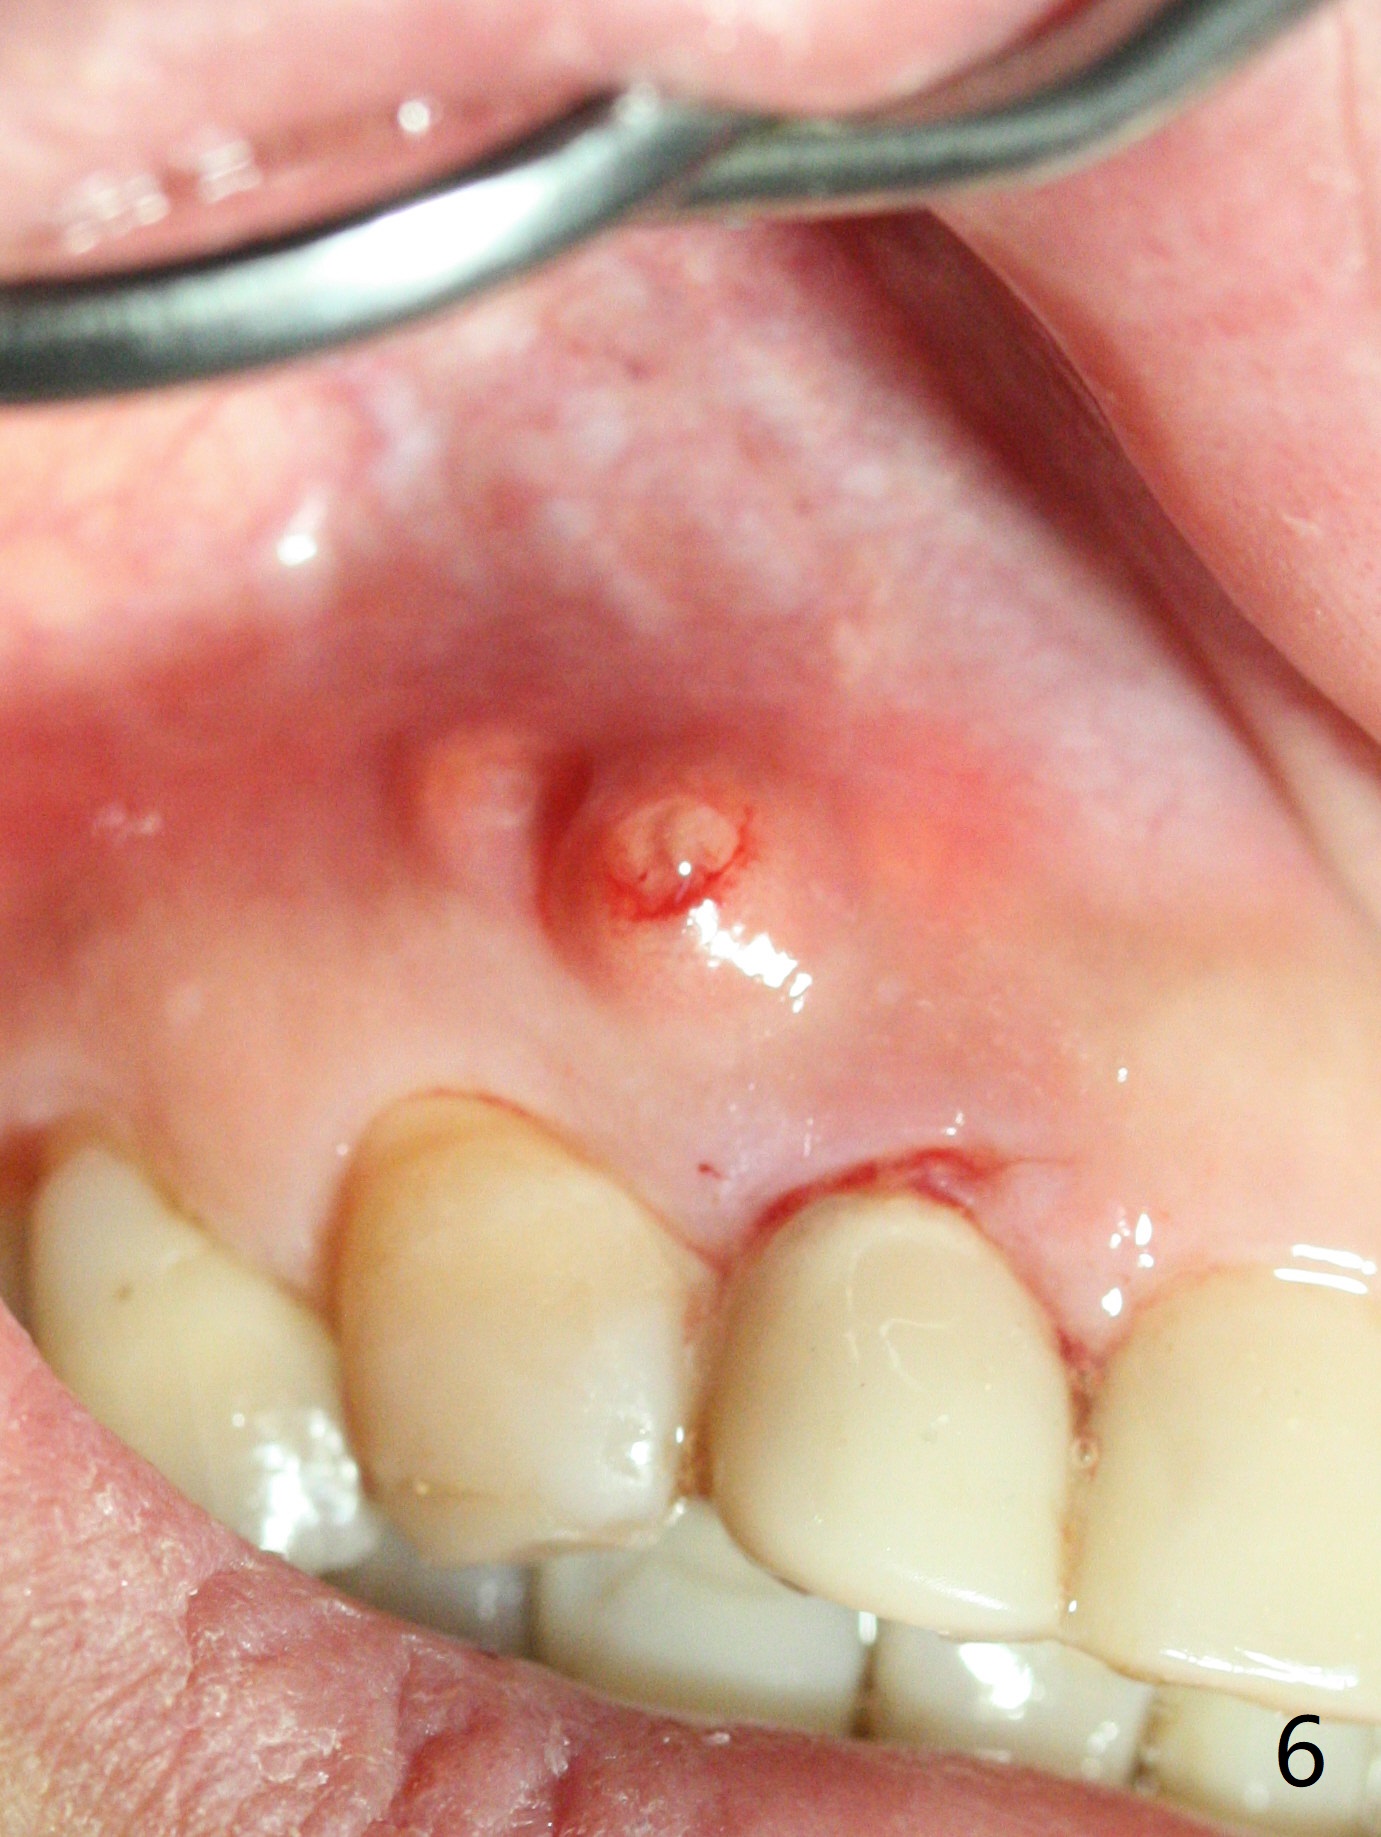

A 47-year-old woman (dental phobic) presented to clinic 9.5 years ago with periapical radiolucency (PARL) at #7 and 9 (Fig.1). RCT was done at #9 because of fistula and symptom 6 months later (Fig.2). While PARL increases at #7 without symptom, that at #9 disappears 8.5 years postop. Three months later, the patient returns for #7 RCT because of the abscesses (Fig.4 *) and pain. Intraop PA is taken with a 30/.06 rotary file in the canal with 19 mm working length (Fig.5). After use of #15 hand file for 20 mm, Ca(OH)2 paste is applied in the canal. When the rubber dam is removed, the abscesses enlarge (Fig.6), which may be related to sodium hypochlorite leakage. A dental explorer is used to try to find a bony opening to the large PARL without success (Fig.7). A postop PA reveals the leakage of Ca(OH)2 paste (Fig.8). Review of the preop PA (Fig.3,9) and intraop PAs (Fig.5,10) shows possible apical resorption and open apical foramen, which is the basis for the paste leakage (Fig.8,11). Careful analysis (with magnification and room light off) of pre- and intra-op PAs should be able to avoid use of #15 hand file out of apical constriction and the complication. The abscess has receded 1 month later (Fig.12). The paste has been resorbed 1 month later (Fig.13). A 30/.06 Gutta Percha is inserted at 18.5 mm (Fig.14 vs. 30/.06 file at 19 mm, 15 file at 20 mm last visit). Fig.15 is the final PA after closure of the access with composite (Fig.15).